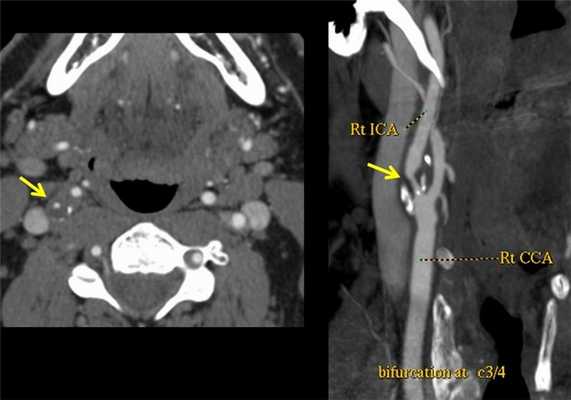

Что выявляет КТ-ангиография. Патологическая извитость внутренних сонных артерий в шейном сегменте (С1). Хорошо виден ход сосудов, можно оценить их диаметр, состояние стенок. Трехмерная (3D) реконструкция сосудов.

Как выглядит атеросклероз на КТ? Ангиография выявляет сужение правой внутренней сонной артерии атеросклеротической бляшкой. Исследование также позволяет наиболее точно изменить степень сужения сосуда (процент стеноза по методикам ESCT или NASCET). Ангиографию обязательно делать людям с выявленной патологией сосудов на УЗДГ, а также пациентам с повторяющимися инсультами.